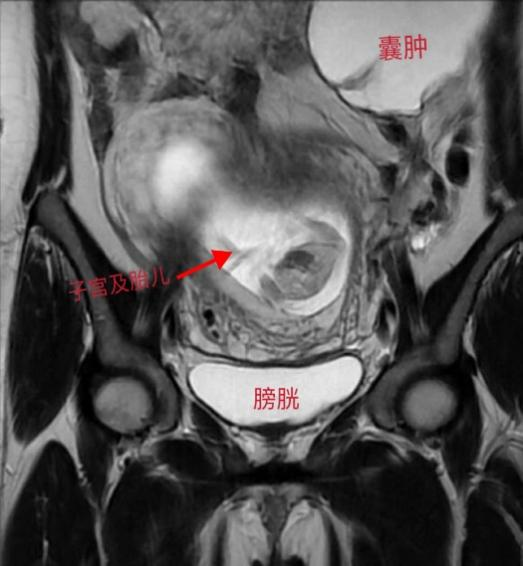

张女士已怀孕4个月,突发下腹疼痛难忍,行B超检查发现怀孕增大的子宫前方有一大约8厘米的卵巢囊肿发生扭转,通常这种情况如不立即手术张女士这一侧的卵巢将会因缺血而坏死需要被切除,妇科接诊后及时给患者施行了单孔腹腔镜囊肿剥除手术,术后张女士宫内胎儿情况良好,腹壁几乎看不见任何伤口,平安顺利出院。